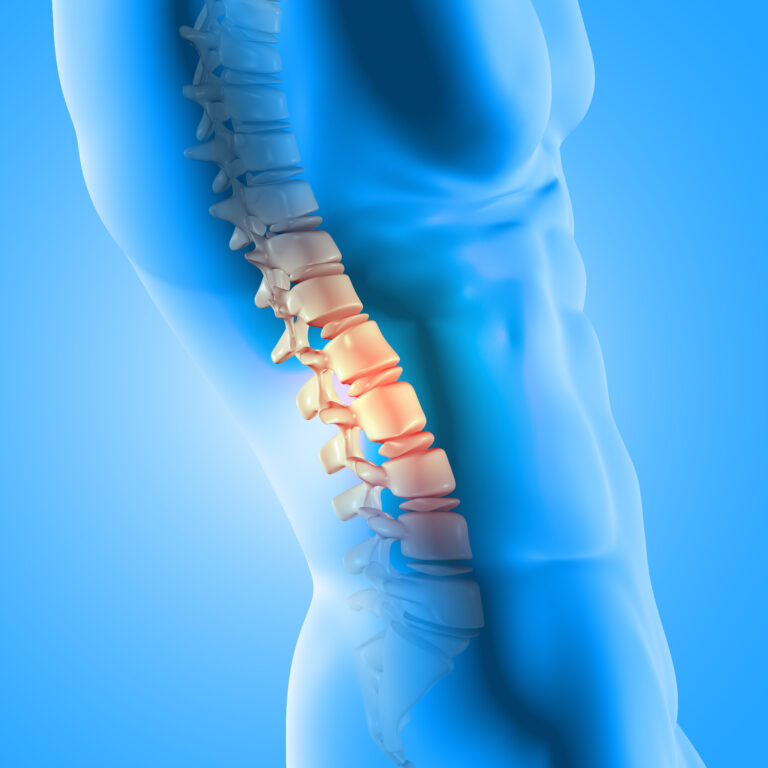

Πάσχω από αγκυλοποιητικη σπονδυλαρθρίτιδα. Οι πόνοι ήταν αφόρητοι εδώ και χρόνια. Κάθε βράδυ για να γυρίσω πλευρό πιανόμουν από το προσκέφαλο για να τα καταφέρω. Το πρωί είχα έντονους πόνους στην μέση οι οποίοι καθιστούσαν αδύνατον να σηκωθώ άμεσα από το κρεβάτι. Έπρεπε πρώτα να μείνω καθιστός για 5 λεπτά και μετά να κάνω κίνηση να σηκωθώ. Ο σβέρκος μου πονούσε τόσο σε σημείο που αν έκανα απότομη κίνηση με το κεφάλι ζαλιζόμουν. Τελικά δεν είναι placibo. Είναι η 6η μέρα από την ημέρα που άρχισα το έλαιο CBD και ως εκ θαύματος οι πόνοι έχουν εξαφανιστεί!! Δεν πονάω. Δεν…